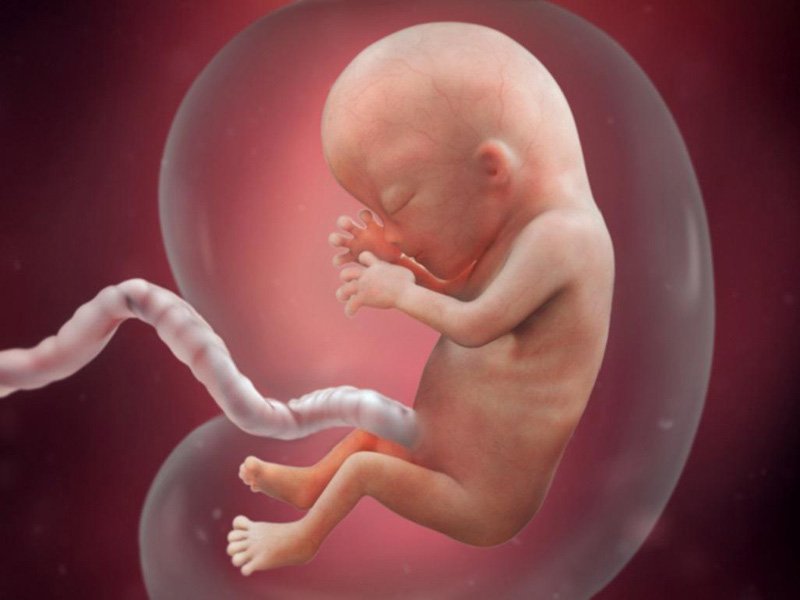

Tháng 3: Thai Nhi Đạt Kích Thước Bằng Quả Chanh

Trong tháng thứ ba, thai nhi đã dài khoảng 7-10 cm và nặng khoảng 20-30 gram.

- Tuần 9-12: Các ngón tay, ngón chân rõ ràng hơn. Xương bắt đầu hình thành, các khớp bắt đầu cử động. Bé đã có thể mút ngón tay cái.

- Tuần thứ 12: Các cơ quan sinh sản bắt đầu phát triển. Bé đã có thể đạp và xoay người. Hệ thống tuần hoàn và tiết niệu hoạt động tốt hơn.